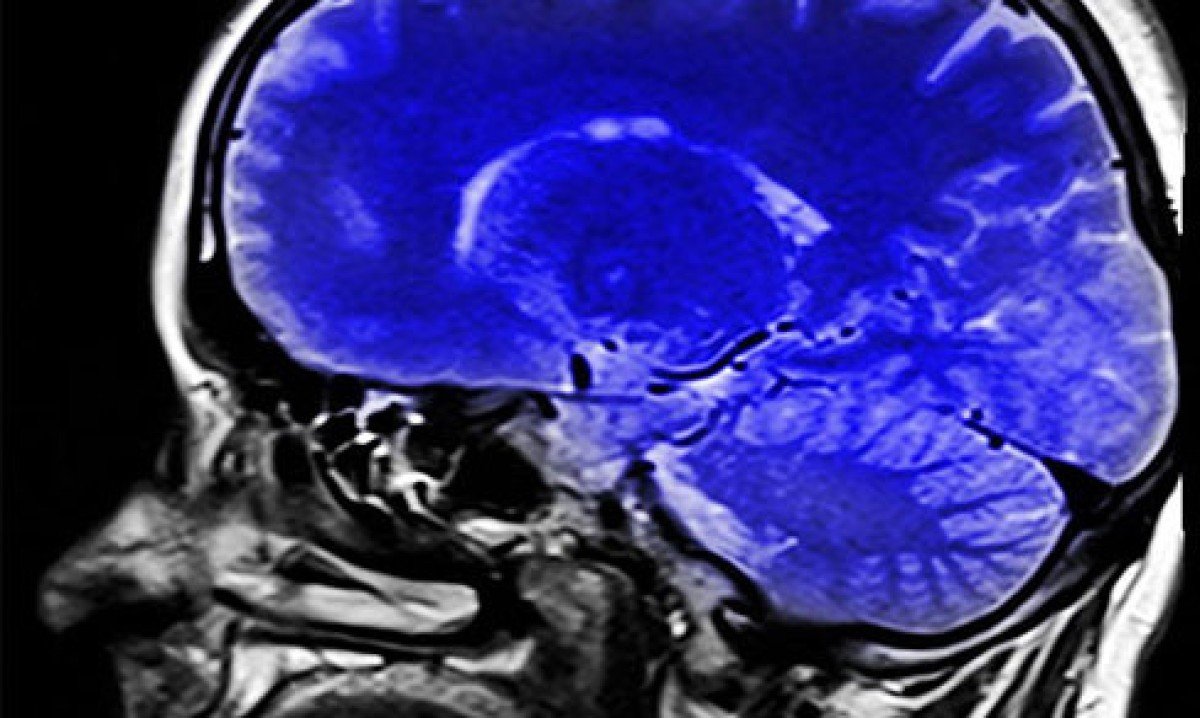

A colina, então, é um nutriente que desempenha um papel crucial no desenvolvimento do cérebro, no funcionamento do sistema nervoso e no metabolismo. Foto: Reprodução -

A colina é importante para que o corpo produza acetilcolina (necessária para o desenvolvimento de memória, pensamento e aprendizado), um neurotransmissor que emite as mensagens do cérebro para o corpo através das células nervosas. Foto: Imagem de Alex Dante por Pixabay -

A deficiência de colina foi associada a doenças neurodegenerativas, como o mal de Parkinson e Alzheimer. Ela é ingrediente presente em suplementos conhecidos como "nootrópicos" Foto: Freepik -